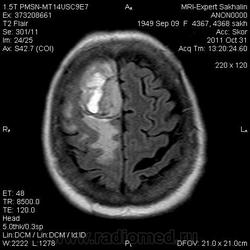

Объем головного мозга.МРТ головного мозга.

Пациентку беспокоят головные боли, нижний парапарез.

менигиома с кровоизлиянием

Это типичная картинка менингиомы?

Это менингиома с кистозным компонентом - кистозная менингиома?

Вообще для менингиом насколько я знаю не очень характерны кровоизлияния, но в данном случае по моему наличие крови в структуре образования не вызывает сомненений...

Да, это уже не первый мой случай менингиомы с кровоизлиянием.

Картина не такая простая на самом деле, не типичная для менингиом. Менингиома, возможно, атипическая менинготелиоматозная. Учитывая такую "пеструю" структуру, перитуморальную реакцию можно сделать вывод вообще об анаплазии...

Но все же признаки менингиомы имеет-прилежание к ТМО,сигнальные характеристики, "дуральный хвост"при контрастировании))))

8й пост. Менингиома с признаками анаплазии.

Сегодня один мой коллега высказал мнение, что образование интрааксиальное и предположил глиому. Как вам такая точка зрения, коллеги?

Легко может быть,поэтому и говорю, что не все так просто и все эти симптомы весьма условны и не типичны для менингиомы. Так можно и до гемaнгиoперицитомы договориться, но это будут лишь предположения.